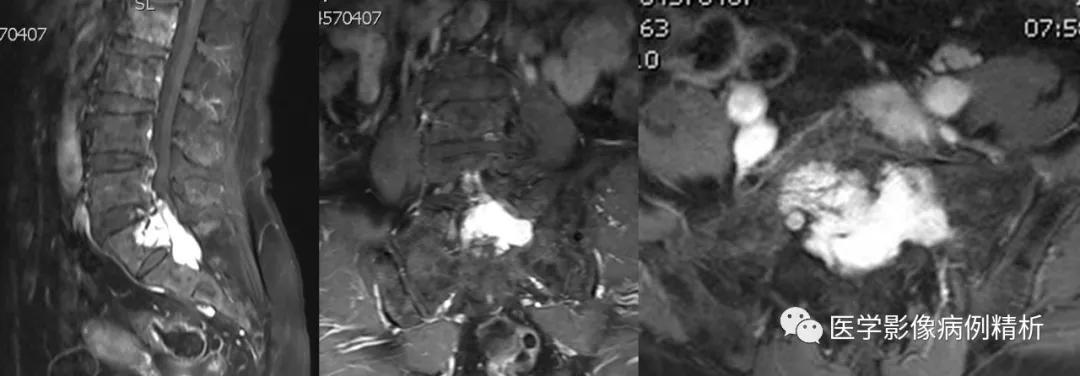

如图所示,红色箭头可见不规则形异常信号,轴位呈哑铃型,病灶前缘侵及骶1、2椎体后缘,绿色箭头见骨质局部破坏,病灶T1低信号,T2稍高信号,压脂像明显高信号,信号尚均匀,腰4-5、腰5骶1椎间盘向后方突出,硬膜囊受压,蓝色箭头可见腰4-5椎间盘后缘纤维化小点状T2高信号,提示纤维环后缘撕裂。本例骶1-2椎间盘形成,骶1椎体腰化不完全。

如图所示,分别为T1WI增强矢状位、冠状位、轴位,T1WI增强矢状位与T2WI压脂像非常相像,注意椎管内脑脊液信号,T1WI增强为低信号与T2WI压脂像高信号正好相反。红色箭头所示病灶明显强化,呈亮灯征感觉,清晰显示病灶范围,绿色箭头所示为病灶侵及骶1椎体后缘形成不规则形骨质破坏区。